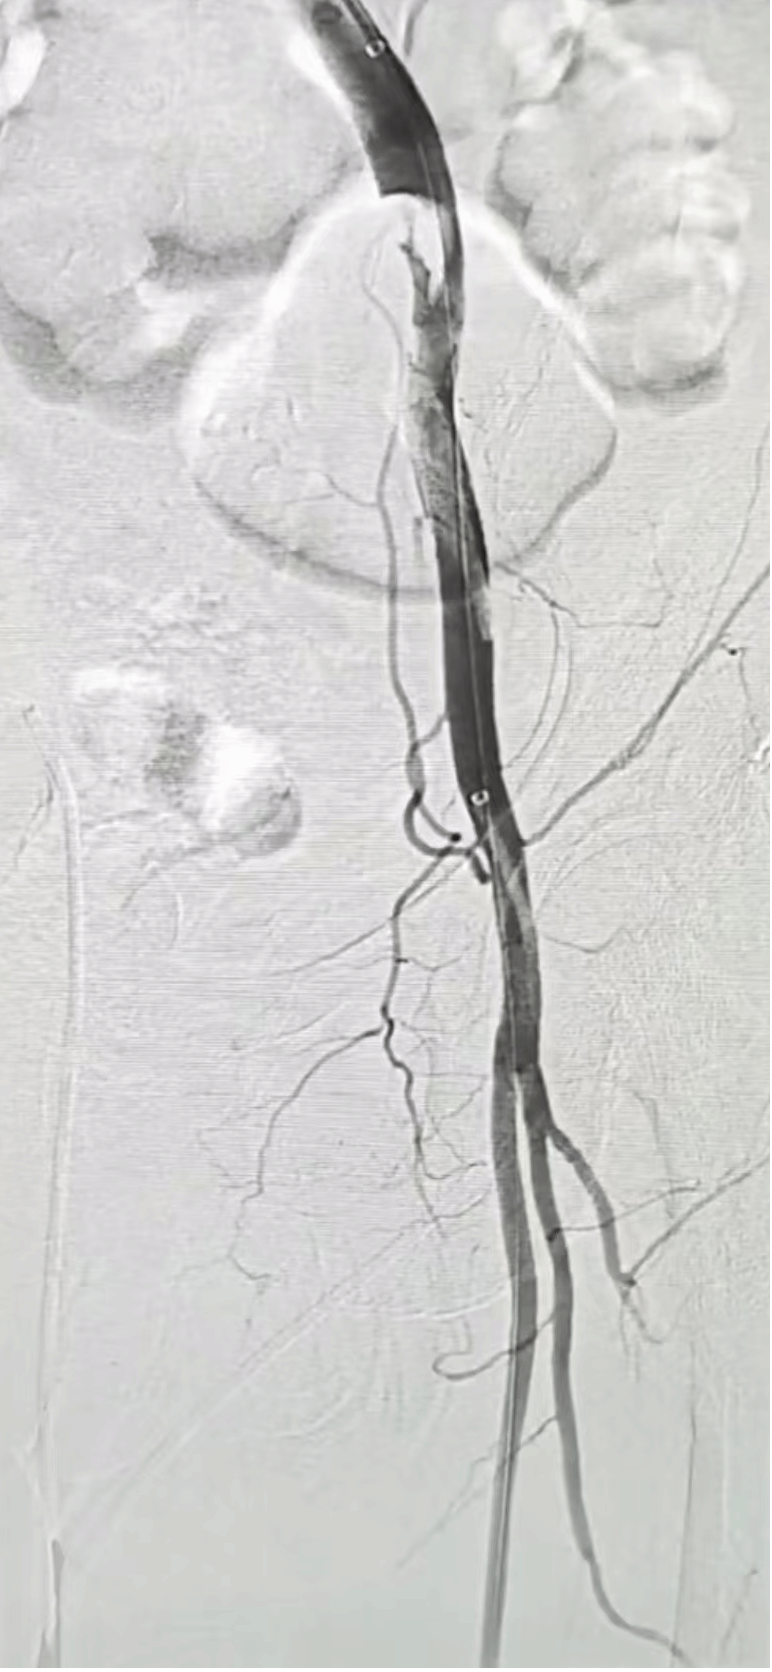

患者术前造影患侧肢体血管完全不显影

开通后的患侧动脉造影